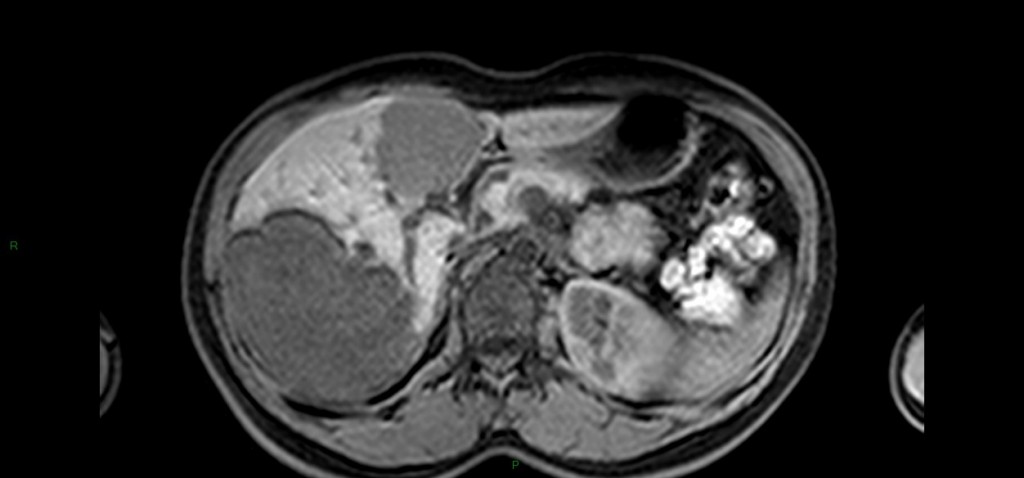

Tumeurs hépatiques – Angiome hépatique Alexandre Ladoux il y a 11 ans ANGIOME CAVERNEUX A reconnaître +++ Unique 90% 80% < 4cm Franc hT1, HT2 liquidien, contours polylobés, disparait en bili-IRM Prise de contraste en mottes discontinues, précoce, avec remplissage centripète (lacs veineux) progressif jusque complet (tardif+++) Possible portion liquidienne centrale : dégenerescence mucoïde ANGIOME CAPILLAIRE (hémangiome) Pdc intense équivalent à l’aorte à tous les temps Diagnostic en échographie : si 4 critères présents Hyperechogène homogène, sans signal Doppler couleur +- renforcement postérieur < 3cm Bilan hépatique normal En dehors de contexte néoplasique DDx : lésions fibreuses avec remplissage centripète: Cholangiocarcinome fibro-lamellaire : Pdc périph mais CONTINUE Métastase d’ADK colique mucineux (HT2 liquidien) ou neuroendocrine : Pdc tardive périph CONTINUE jamais complète Exemples d’angiomes hépatiques Angiome géant Angiomes et adénome graisseux Partager : Partager sur Facebook(ouvre dans une nouvelle fenêtre) Facebook Partager sur LinkedIn(ouvre dans une nouvelle fenêtre) LinkedIn Partager sur X(ouvre dans une nouvelle fenêtre) X Partager sur WhatsApp(ouvre dans une nouvelle fenêtre) WhatsApp Envoyer un lien par e-mail à un ami(ouvre dans une nouvelle fenêtre) E-mail Imprimer(ouvre dans une nouvelle fenêtre) Imprimer Plus Partager sur Tumblr(ouvre dans une nouvelle fenêtre) Tumblr Partager sur Pinterest(ouvre dans une nouvelle fenêtre) Pinterest